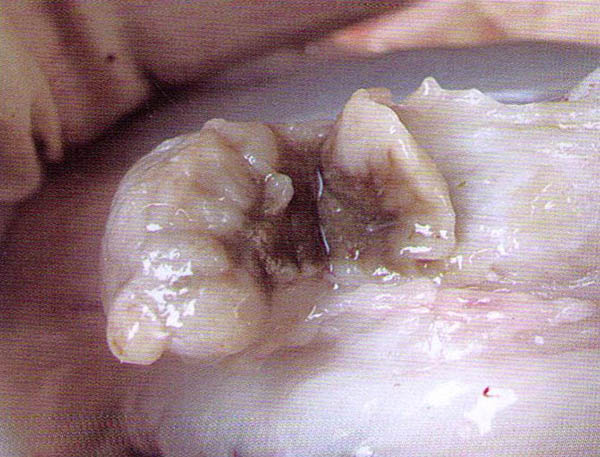

羊链球菌病-羊眼脸、喉咙、颌下淋巴肿大